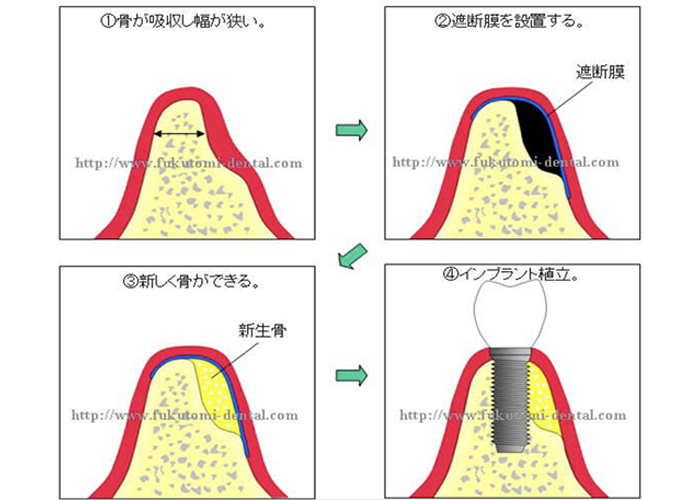

GBRの歯科インプラントへの応用。骨造成を併用したインプラント症例 - 相模原市矢部の歯医者。さかもと歯科医院】GBR、人工骨について | さかもと歯科医院。インプラントのご相談は、博多の「加茂歯科医院」へ。

「GBRの歯科インプラントへの応用」DanielBuser / 中村社綱定価: -#DanielBuser #中村社綱 #本 #自然/医療・薬学・健康